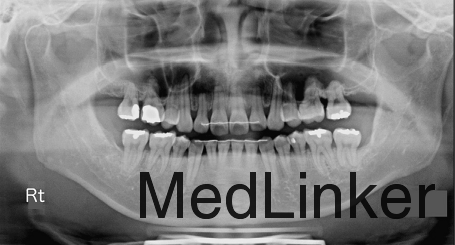

男,31岁,要求关闭牙弓内间隙

凸面型,骨性II类,青少年期拔除了3颗前磨牙但由于其他原因未继续矫正,深覆合,覆盖5.5mm,右侧磨牙I类,左侧磨牙II类关系,双侧尖牙II类

诊断:骨性II类,安氏II类,牙列间隙 治疗:上颌先上.022直丝拖槽,14niti排齐整平,依次换丝,为打开前牙咬合,16*22TMA弯制压低辅弓,如图。打开咬合后,粘接下颌拖槽,继续矫正。